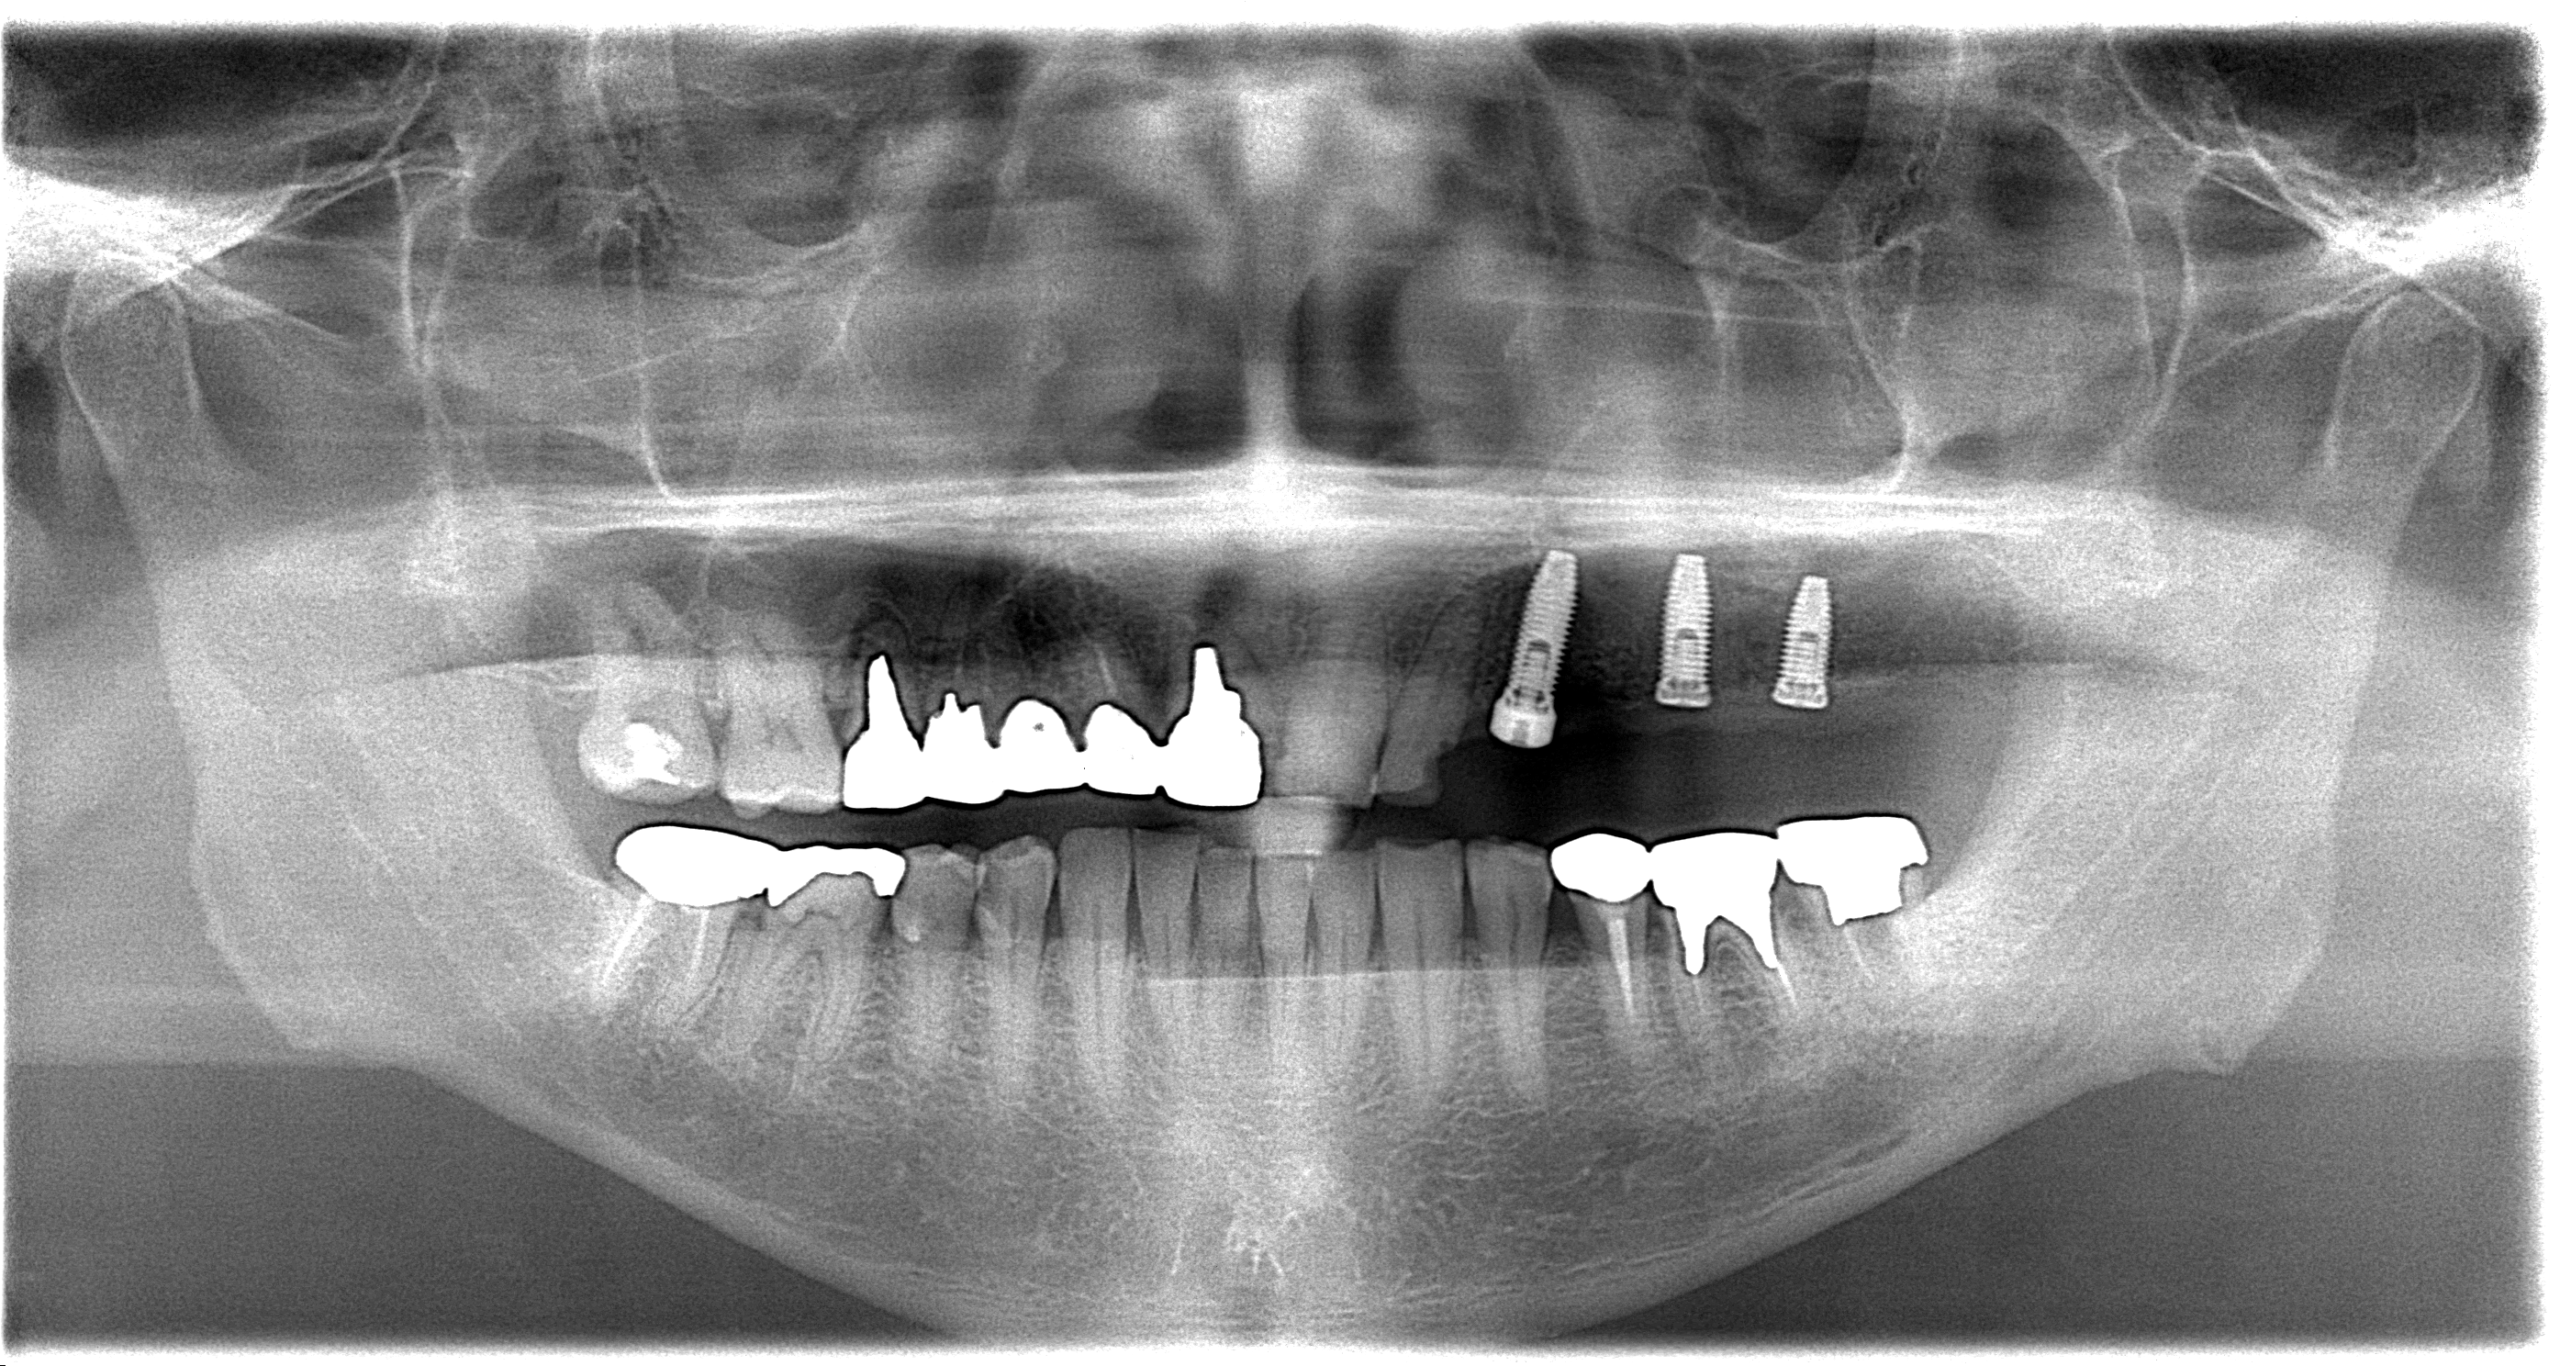

歯周病検査

歯周病の治療を開始する前には、正確な診断が不可欠です。

歯周病検査はプロービング、動揺度と出血の検査を行います。

プロービングでは歯周ポケットの深さを測定し、同時に出血したかどうかの確認も同時に行います。

歯の動揺度の検査も行い、歯周病の進行度を確認します。

歯周病検査は定期的に行うため、その時の歯周病の進行度が分かるだけでなく、患者様の経時的な歯周組織の変化や、治療の効果を把握できます。

これにより、適切な治療計画と効果的な治療につながります。